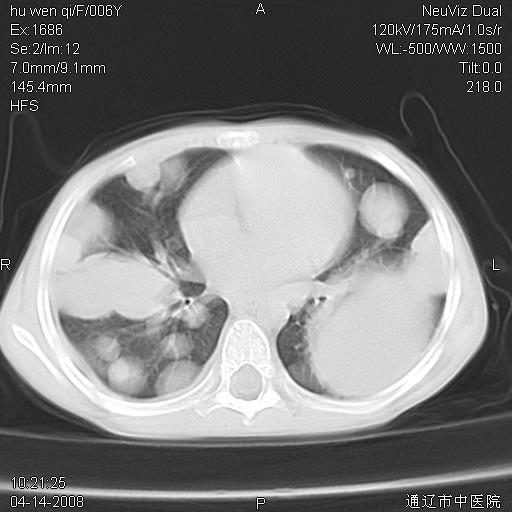

女, 6岁 ,反复咳嗽2周,近两日发热伴右侧胸痛

两肺多发似葡萄状大小不等高密度区,边界清楚,部分见薄壁空洞。左胸壁后方见局限性高密度区,边界清楚,广基与后侧胸壁相连。

考虑:1、金黄色葡萄球肺炎(血源性);

2、左侧包裹性积液;

3、建议严格抗炎治疗后复查。

谢谢各位的诊断意见,结果已经出来了,是神经母细胞瘤肺转移,原发病灶在肾,现在已进行放、化疗。

原发应该是在肾上腺